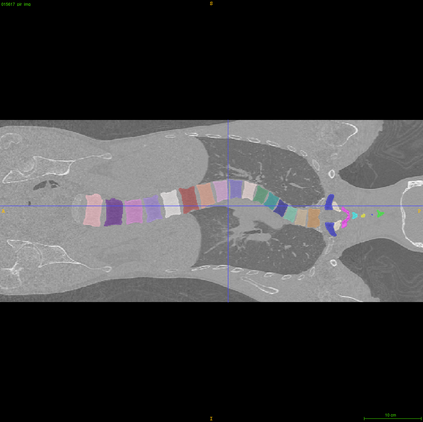

Vertebrae localization, segmentation and identification in CT images is key to numerous clinical applications. While deep learning strategies have brought to this field significant improvements over recent years, transitional and pathological vertebrae are still plaguing most existing approaches as a consequence of their poor representation in training datasets. Alternatively, proposed non-learning based methods take benefit of prior knowledge to handle such particular cases. In this work we propose to combine both strategies. To this purpose we introduce an iterative cycle in which individual vertebrae are recursively localized, segmented and identified using deep-networks, while anatomic consistency is enforced using statistical priors. In this strategy, the transitional vertebrae identification is handled by encoding their configurations in a graphical model that aggregates local deep-network predictions into an anatomically consistent final result. Our approach achieves state-of-the-art results on the VerSe20 challenge benchmark, and outperforms all methods on transitional vertebrae as well as the generalization to the VerSe19 challenge benchmark. Furthermore, our method can detect and report inconsistent spine regions that do not satisfy the anatomic consistency priors. Our code and model are openly available for research purposes.